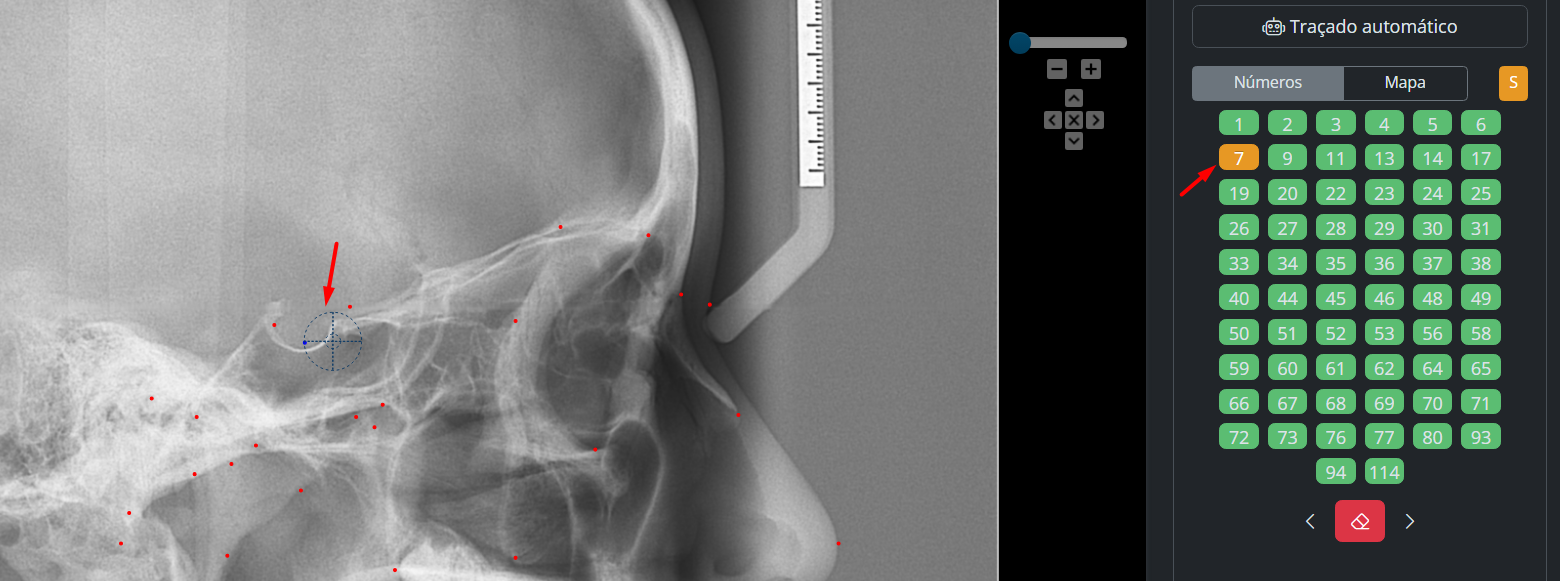

Nesta aba, é realizada a marcação dos pontos cefalométricos.

Você pode:

- marcar manualmente

- utilizar o traçado automático

Marcação manual

Para marcar:

- Clique com o botão esquerdo no local desejado

- O sistema avançará automaticamente para o próximo ponto

Abaixo, você encontrará:

- quadro de números

- mapa de referência (auxilia na localização dos pontos)

Correção de pontos

Para corrigir:

- selecione o ponto no quadro de números

- clique novamente na posição correta

Ou:

- utilize o ícone de borracha para apagar

Alguns pontos, como a Sela (S), possuem ajuste fino, permitindo pequenas correções manuais para maior precisão na marcação.

- clique com o botão direito

- arraste para reposicionar